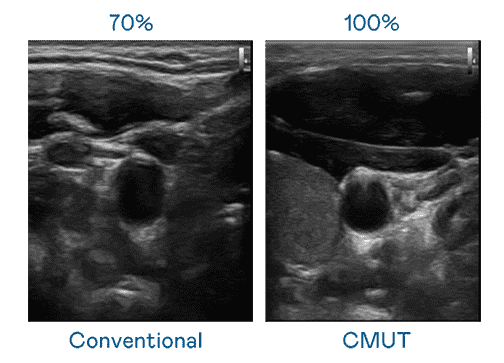

CMUT 技术是一种用电容式微机电元件来产生超音波讯号的技术。。。与传统 PZT 压电式技术相比,,,,CMUT 频宽增加 30%,,,更宽频的超音波讯号让影像解析度大幅提升,,,,是实现高影像品质医疗超音波扫描、、、促进精准医疗发展的关键技术。。。。

大频宽带来超清晰影像

超音波影像的解析度高低,,,首先取决于探头能发出的讯号频宽。。口袋牛店 CMUT 可提供高清晰的超音波讯号,,,提供高频宽、、、、高灵敏度、、影像纹理细节更高的超音波影像,,协助医护人员缩短影像判读时间及利用精准的医疗影像进行诊断。。